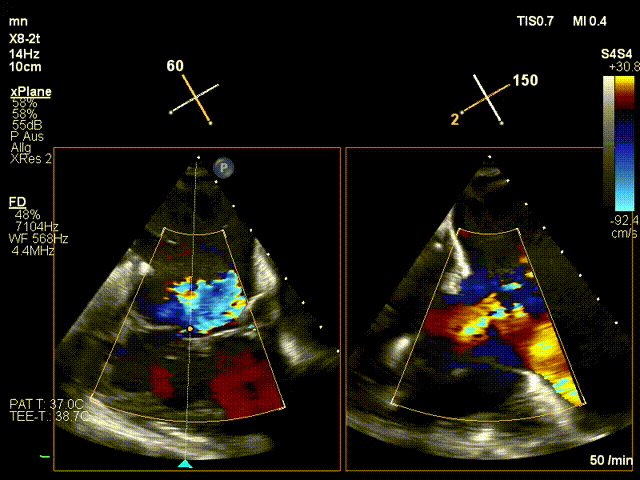

手術(shù)在全麻狀態(tài)下進(jìn)行。在加拿大圣保羅醫(yī)院的Anson Cheung教授的指導(dǎo)參與下,術(shù)者采用經(jīng)右側(cè)頸靜脈入路的方式將輸送器送入患者心臟內(nèi),在TEE及DSA引導(dǎo)下調(diào)整輸送器頭端角度,使得輸送器與三尖瓣瓣環(huán)平面垂直。在輸送器進(jìn)入右心室后釋放室間隔錨定裝置,而后釋放瓣葉夾持件(2個(gè)耳片結(jié)構(gòu))成垂直狀態(tài)。在TEE及DSA確定夾持件固定至三尖瓣葉根部且位于右室側(cè)后釋放人工瓣心房側(cè)盤片。隨后調(diào)整瓣膜同軸性以及室間隔錨定件位置(貼合室間隔),前推藏針管并固定,進(jìn)而釋放室間隔錨定裝置,并再次確認(rèn)瓣膜位置、穩(wěn)定性及同軸性,合攏輸送鞘后撤出輸送器,完成LuX-Valve Plus人工三尖瓣瓣膜的植入。

LuX-Valve Plus經(jīng)血管三尖瓣置換系統(tǒng)本次“出海”圓滿完成,術(shù)后Jörg Hausleiter教授對LuX-Valve Plus經(jīng)血管三尖瓣置換系統(tǒng)的器械性能和治療效果大為稱贊,認(rèn)為LuX-Valve Plus的手術(shù)體驗(yàn)非常好。術(shù)后即刻超聲顯示三尖瓣反流消失,血流動(dòng)力學(xué)改善顯著,患者恢復(fù)快。Anson Cheung教授也肯定了LuX-Valve Plus術(shù)中操作的便捷性,認(rèn)為LuX-Valve Plus容錯(cuò)率高,對術(shù)中影像的依賴較小,后期希望可以更多的應(yīng)用LuX-Valve Plus三尖瓣置換系統(tǒng)于臨床實(shí)踐,讓更多的三尖瓣重度反流患者盡早獲益,改善預(yù)后。